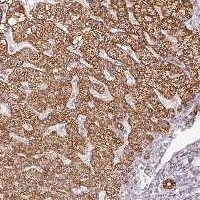

PQLC2L